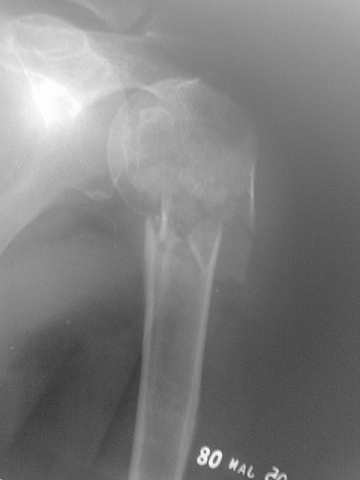

This fx need to be manipulated, reduced and fixed. We developed a minimally invasive ex fix with Ilizarov parts to fix it, we call it “Spider”, which can hold 4 fragments.

Attaching a case.